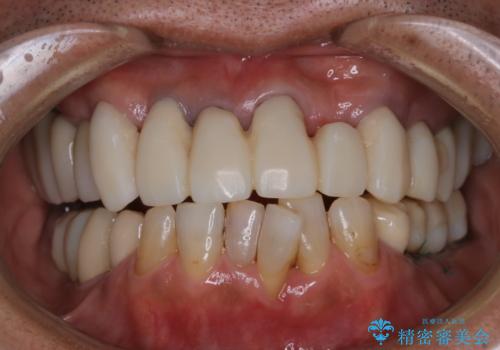

[エアフロー] スプレーの噴射によりしつこい色素沈着やプラークを除去

担当医 歯科衛生士

![[エアフロー] スプレーの噴射によりしつこい色素沈着やプラークを除去の症例 治療前](https://seimitsushinbi.jp/wp/wp-content/uploads/2021/11/IMG_9998-500x350.jpg?v=1636593297)

![[エアフロー] スプレーの噴射によりしつこい色素沈着やプラークを除去の症例 治療後](https://seimitsushinbi.jp/wp/wp-content/uploads/2021/11/IMG_0004-500x350.jpg?v=1636593307)

エアフローによるクリーニング